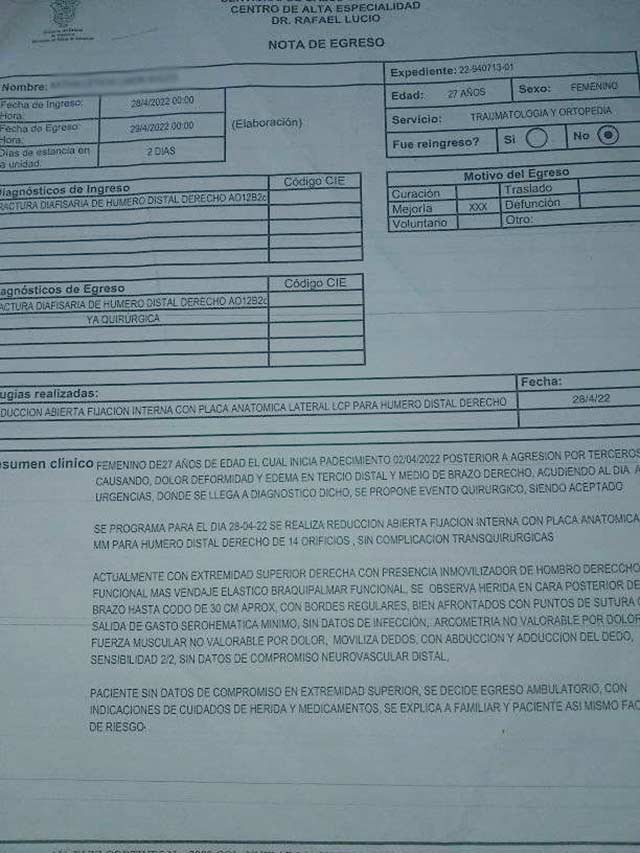

El día 1 de abril del presente año fui brutalmente golpeada por un hombre, si así se le puede llamar al cobarde que me ocasionó esto. A consecuencia de estos brutales golpes resultó con coágulos en mi cabeza, un brazo derecho roto y múltiples hematomas.

En estos meses no he podido trabajar como normalmente lo hacía ya que requerí de una cirugía en mi brazo en la cual me colocaron una placa y varios clavos, pero mi cuerpo los a rechazado desde el primer día. Ya han pasado 6 meses y los insoportables dolores continúan y la infección no desaparece.

Me tienen que realizar una nueva cirugía por la infección que no se ha podido controlar pero para realizarla me piden un estudio que tiene en costo de $1,500 dinero, que por el momento no tengo. Estoy muy preocupada ya que los doctores me han dicho que si la infección no cesa y entre más tiempo deje pasar podría perder mi brazo.

Adjunto los documentos que constatan las intervenciones a las que he sido sometida y tarjeta en la cual puedo recibir de su ayuda a nombre de Julio Solorza y número de contacto 2283467611 por si alguien gusta apoyarme, lo que sea será bien recibido y con muchísimo agradecimiento.